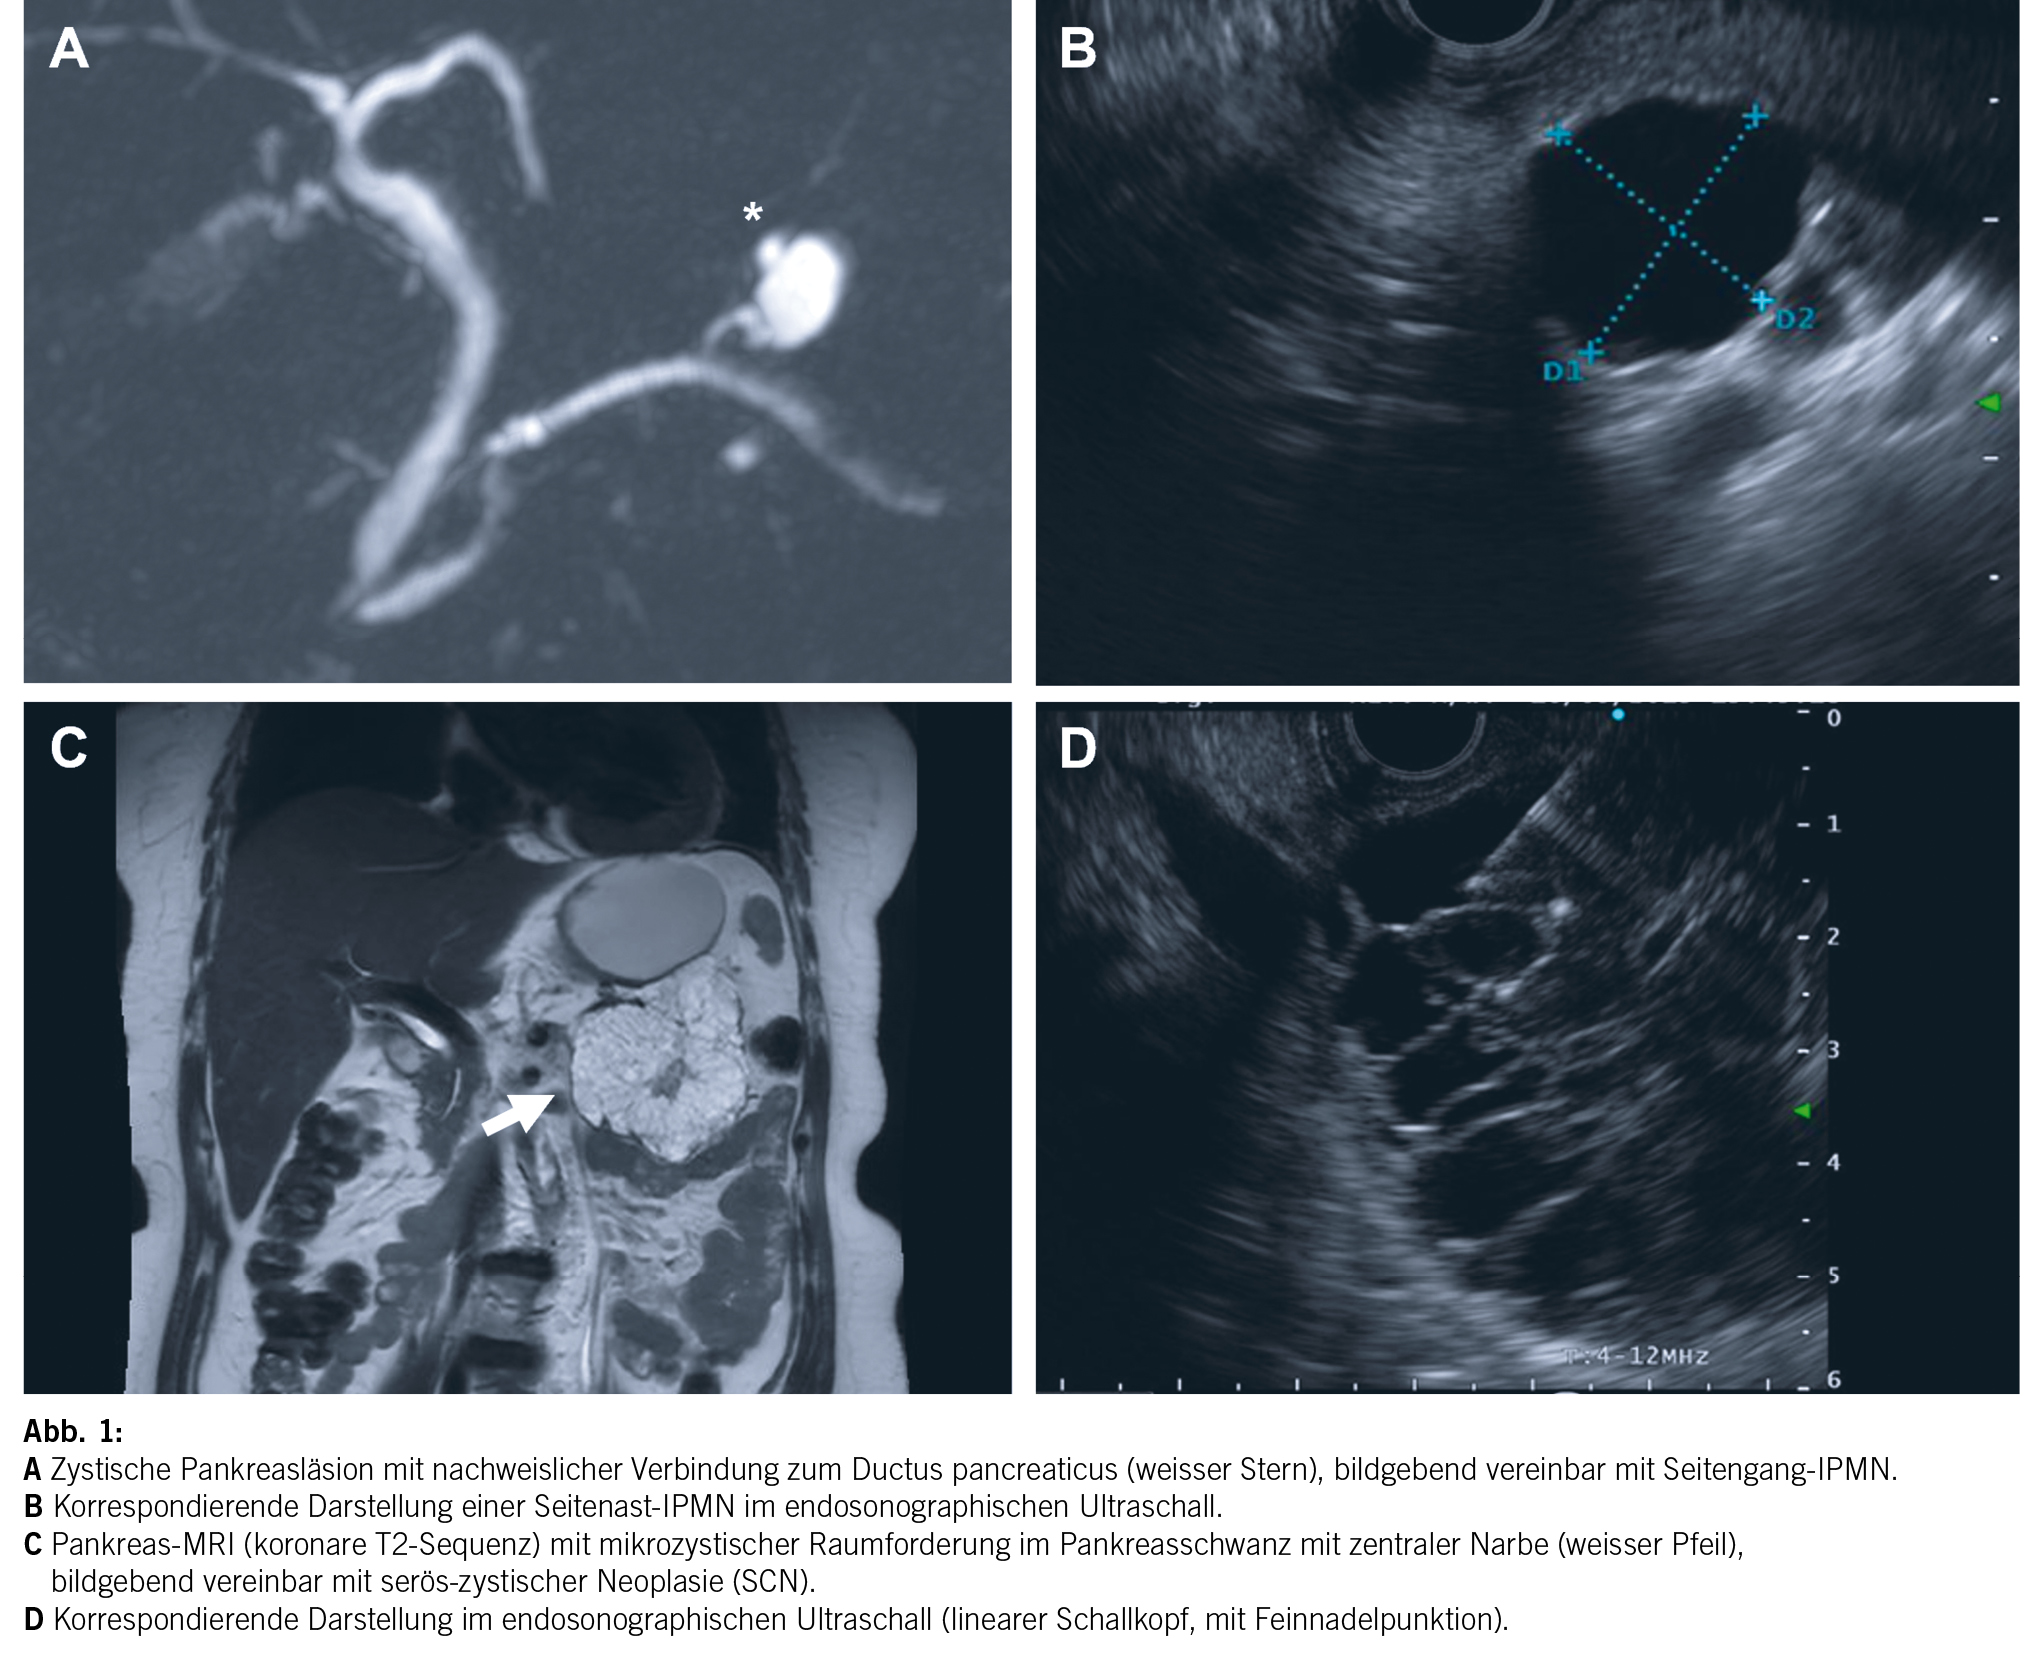

- Zystische Pankreasläsionen – wie abklären und überwachen?